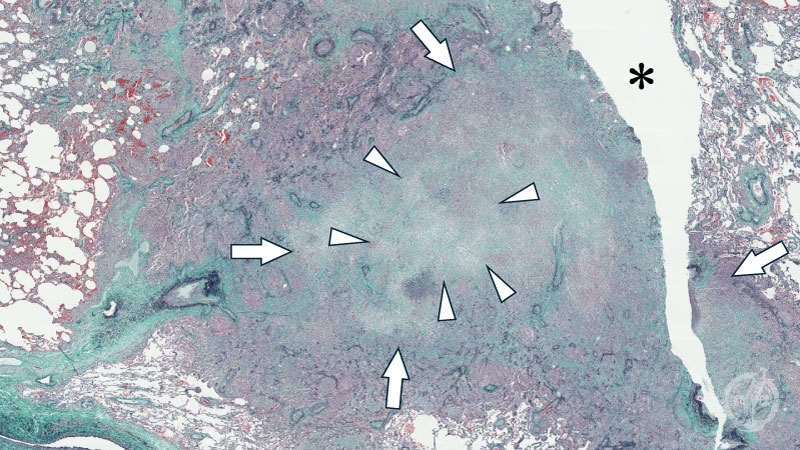

ミクロ像 (Elastica-Masson染色 弱拡大):肺実質の破壊、空洞形成(*)を伴う壊死性肉芽腫性病変。弾性線維の消失(矢印)とともに無構造な壊死組織(矢頭)を認める。